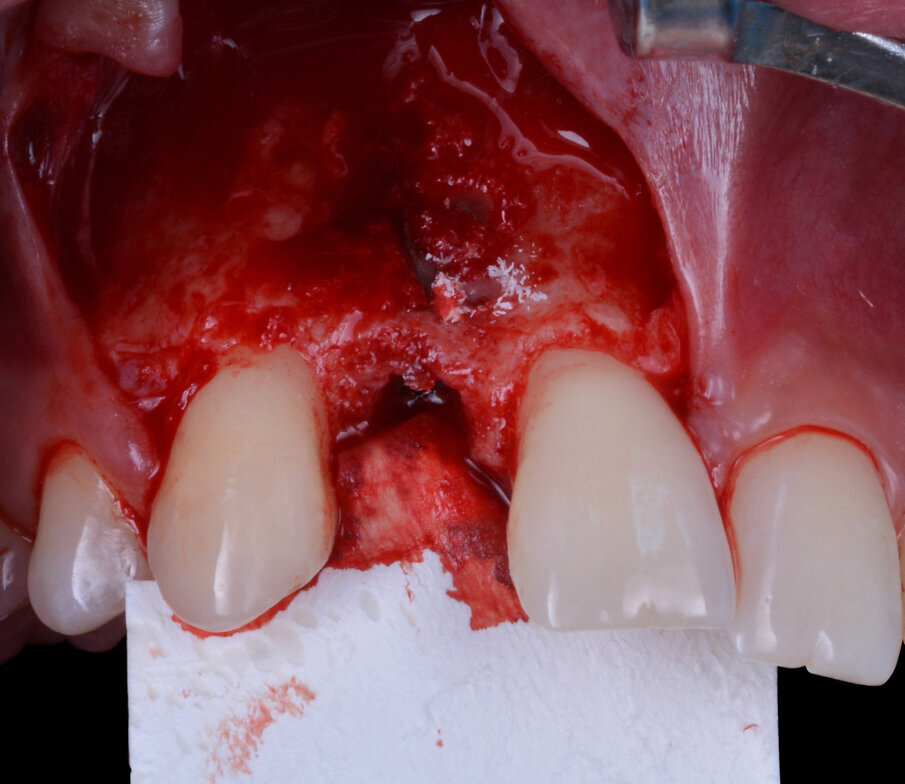

Ad inserimento della fixture avvenuto si rileva la presenza di una piccola fenestrazione vestibolare classificabile come un’atrofia vestibolare di Classe II secondo la classificazione di Chiapasco e Casentini dei difetti ossei perimplantari del 20188 (Fig. 6). La tecnica chirurgica scelta per la gestione del difetto osseo è la GBR. Il primo step contempla di eseguire dei fori di osteopromozione sulla corticale vestibolare attraverso uno strumento rotante a basso numero di giri e senza ausilio di irrigazione con acqua fisiologica così da ottenere un maggior apporto ematico endostale nella regione da trattare e la successiva aggiunta di particolato di osso autologo che conferisca osteoinduttività e osteogeneticità all’innesto (Fig. 7). Il difetto viene gestito impiegando scaffold inorganici, ovvero dei biomateriali che fungono da riempitivi inerti con proprietà osteoconduttive (in grado di guidare la rigenerazione ossea facilitando la stratificazione e l’organizzazione del coagulo su di essi) e di space making (capaci di mantenere lo spazio necessario alla rigenerazione impedendo il collasso parziale o totale dei tessuti molli sovrastanti)9. Nel caso specifico, il biomateriale eterologo innestato è di origine bovina (Nobel Biocare Xenogain 0,2-1 mm); dopo l’accurato posizionamento del biomateriale nella regione da trattare si procede alla protezione dello stesso con una membrana riassorbibile in pericardio bovino con matrice tridimensionale (Ubgen, Shelter/sistema Pericross) stabilizzata per mezzo di pins di fissazione sia palatalmente che vestibolarmente (Fig. 8). L’esecuzione di un’incisione di rilascio periostale del lembo vestibolare permette di ottenere una chiusura per prima intenzione della ferita caratterizzata da una competente interfaccia dei due lembi e da una passivazione degli stessi (Fig. 9). La dimissione della paziente avviene solo dopo aver applicato con cementazione adesiva il Maryland bridge provvisorio prestando particolarmente attenzione a evitare compressioni sui tessuti molli appena trattati chirurgicamente. Durante il periodo di guarigione la paziente viene rivalutata con cadenza mensile per controllare il procedere del fisiologico decorso post-operatorio. A 6 mesi dall’inserimento dell’impianto, dopo opportuni controlli radiografici, si procede con la programmazione della riapertura.

Fig. 7 - Osso autologo particolato ottenuto durante l’esecuzione di fori di osteopromozione.

Fig. 8 - Stabilizzazione del complesso innesto-membrana.